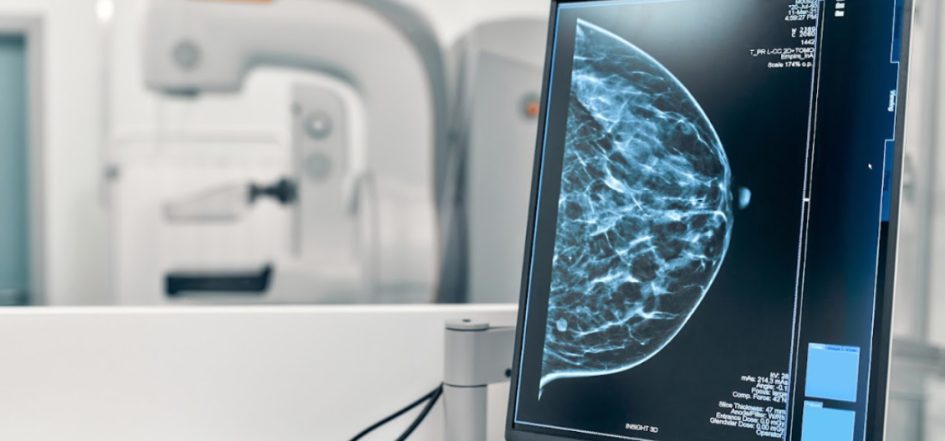

“Estas implementaciones han permitido aumentar el diagnóstico con la realización de mamografías gratuitas, a la cual pueden acceder mujeres entre los 50 y 59 años, cada 3 años, para detectar el cáncer de mama”, explicó Gutiérrez a EFE.

Los expertos indican la importancia de realizarse, a partir de los 40 años, de manera anual la mamografía y ecotomografía correspondiente.

“De manera regular se hacen campañas de concienciación en la prevención del cáncer de mama, con el objetivo de adoptar conductas de autocuidado, como el autoexamen de mama y la realización de exámenes médicos preventivos que incluyen la mamografía”, indicó la especialista de la UDP.